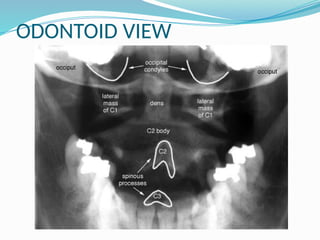

ODONTOID VIEW

 The open-mouth odontoid view shows a lateral mass

rotated anteriorly and toward the midline .

 The joint space of the lateral mass rotated

posteriorly appears to be overlapping the one below.

 The C2 spinous process is rotated off the midline on

the anteroposterior view.

 Failure of C1 to reposition on a left-and-right

rotation

 CT also shows that the dens separates from the

anterior arch of C1 with increased rotation